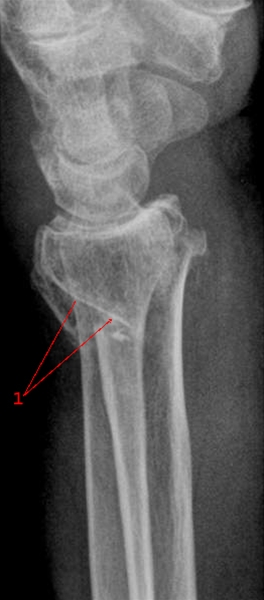

Radiusfraktur, side

Fraktur (pil) gennem distale radius med dorsal vinkling af distale fragment.